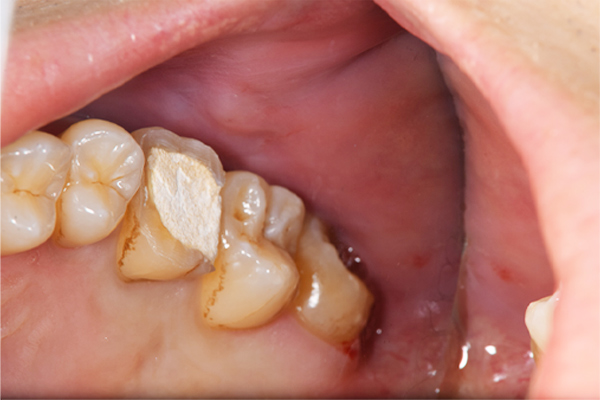

こちらは、下顎の親知らずが半埋伏で斜めにはえています。また、前の歯との間に虫歯をつくってしまっていたり、前の歯の根の先端の方まで骨が溶けてしまっています(智歯周囲炎)。

このように他の残さないといけない歯に悪影響を与えている親知らずに関してはなるべく早めに抜いたほうがよいです。

上顎の親知らずの抜歯のBefore/Afterです。抜歯時間は10分です。上顎の抜歯はほとんど腫れることもないです。リスクとしては一番最初の症例のように上顎洞への穿孔です。ただし、穿孔したとしても、鼻をつよくかむなどせず、安静にしていれば、しっかり回復しますので安心してください。抜歯費用は約1,700円(保険適応)

です。

下顎の親知らずの抜歯のBefore/Afterになります。歯ぐきの中に埋まっていましたが、歯ぐきを切ることなく、低侵襲に手術を終えられました。抜歯時間は10分です。下顎は斜めにはえている親知らずを抜く場合は歯ぐきを切ったり、親知らずの周りの骨を削ることが多いので、術後1週間くらい腫れることが多いです。

また、下顎は、親知らずの根の先端が顎の骨のなかにある神経と近いことが多いです。神経と根の先がくっついている場合は抜く際に注意が必要となります。抜歯費用は約7,500円(保険適応、CT撮影込)です。